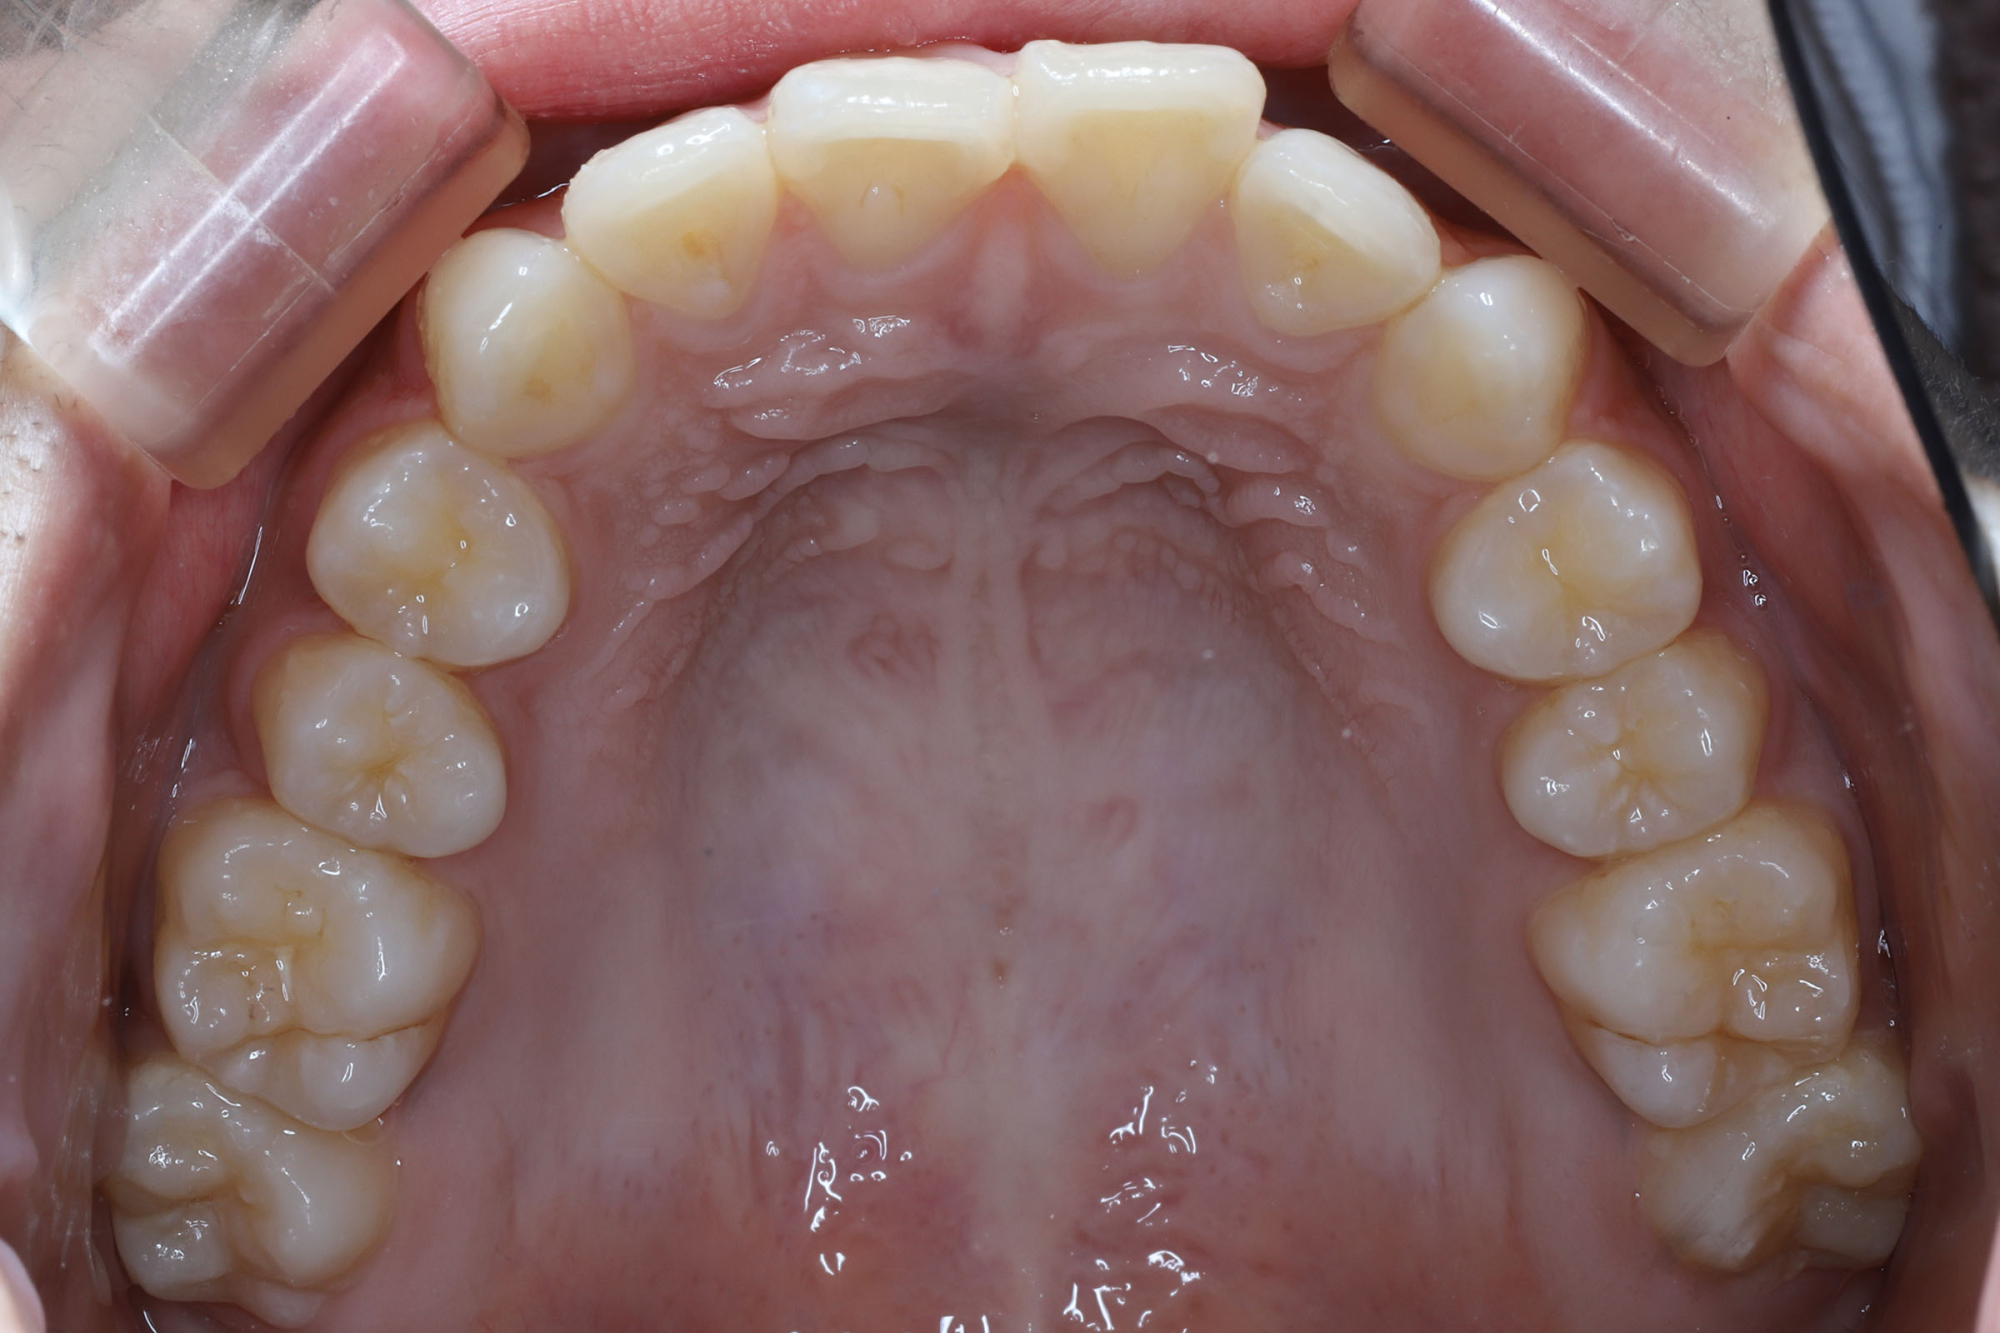

日本で行われている拡大床治療にも色々な方法がありますが当院での特長は最初に永久歯に生え替わる上下4本の前歯を奥歯の生え替わりが始まる前までに顎を拡大してきれいに並べることです。そのため拡大床治療の期間は小学校1年生頃から4、5年生頃までの間に限定しており、それまでに目的が達成できない場合には別の治療法に移行します。またゆっくりスペースを獲得するようにしているのも特長で2週間に1回ネジを回すようにしています。一般的には1週間にⅠ回ないし2回ネジを回すことが多いようです。ゆっくり進めるので一日の装着時間はお家にいるときと寝ている間だけにしています。学校や自宅以外での装着はせずゆっくり拡大していくので治療期間が長くなりますが後戻りは少なく確実になります。治療開始時期が大切ですので時期を逸した場合には拡大床治療は行いません。一般的に拡大床治療の評判が悪いのは開始時期が遅く、いつまでも治療を長引かせ治らないことによるものが多いようです。 拡大床治療はスペースを作って永久歯がならぶスペースを作ることが目標ですので細かい歯の向きや角度まで整えられないこともあります。そんな場合には別の矯正治療が必要になります。

拡大床治療ではすべての歯がきれいに並ぶように顎の成長を促すことが目的ですので細かい歯の位置や角度までは調整できません。また歯が大き過ぎる場合には口の中で歯が目立ちすぎることになる場合もあります。日本人を含めたアジア系の骨格には特長があり、ヨーロッパ系の顔立ちとは基本的に違っていますが上下の歯を抜いたりすることでそれに近づけることもできます。矯正専門の歯科ではそのような目標を立てて治療を行うことが多く、そのために4本の永久歯を抜歯することもあります。拡大床治療では歯を抜かずすべての自分の歯でしっかり噛めることを目標にしていますので口元のきれいさを目的にする治療とは異なります。歯を抜いて口元をきれいにするのは大人になってもできる治療ですので、親としては先ずはお子さんのすべての歯を使ってきれいに歯をならべることを優先すべきで、あとで本人が口元が気になるというのであれば本人の意志で歯を抜いて矯正治療を行うべきであるというのが当院の考えです。

拡大床治療は矯正治療ではありませんので完璧にきれいな歯ならびにできるわけではありません。また治療期間も長くなり期間限定の治療法ですので小学校の高学年になってから始めるのには向いていません。また拡大床治療で歯を並べる顎は拡がりますがエラの張った大きな顔になるわけではありません。歯を支える骨は歯槽骨、下顎全体は下顎骨と言って解剖学的には別の骨と考えられています。エラが張った大きな顎になるのは遺伝的な要素や咬む力が大きく影響します。拡大床治療を行ったからといって顎全体が大きくなるわけではありません。